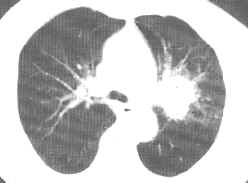

左上叶中央型肺癌。CT平扫肺窗(上图)示左肺门肿块,边缘略有分叶及细短棘状突起。增强纵隔窗(下图)示肿块略有强化,密度不均,强化程度明显低于邻近的左肺动脉。手术及病理证实为低分化鳞癌。